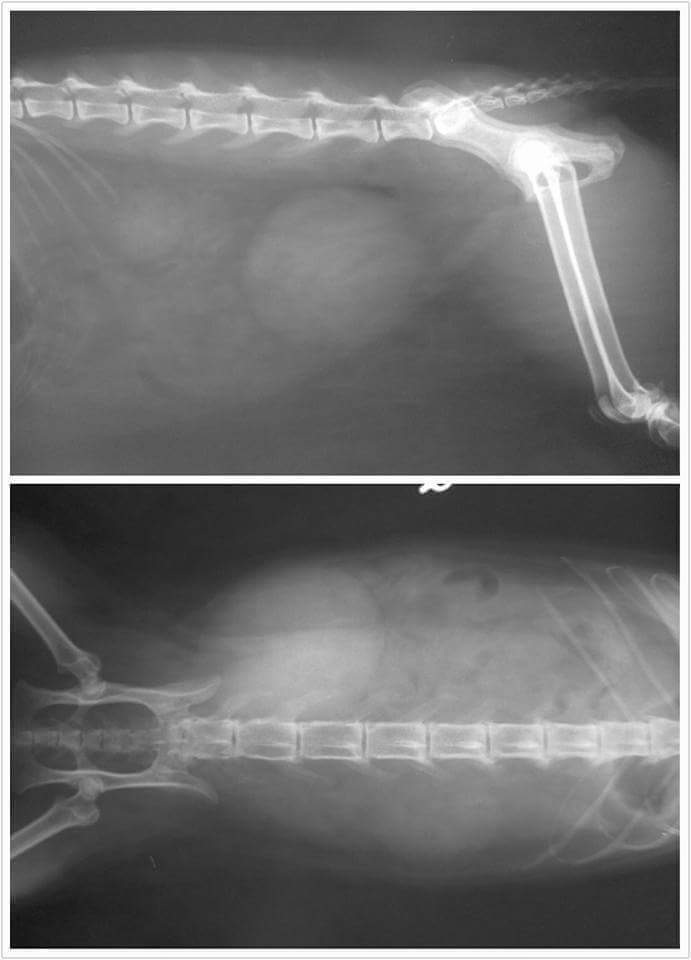

醫生說熊熊檢查後膀胱過大且尿道堵塞無法排尿,初步已先導尿並輸液治療,驗血發現白血球及腎指數過高,且鉀離子也過高,顯示排尿受阻已影響到腎臟,X光檢查並無發現結石但超音波下檢查發現膀胱壁變厚有發炎的跡象,且有尿中有晶體,尿液會送驗做細菌培養。

4.X光檢查 400×2=800